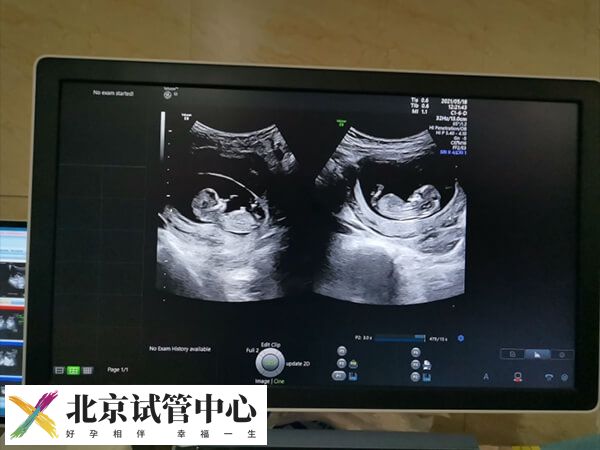

- 移植两个胚胎,两个都着床了,异卵双胎;

- 移植两个胚胎,一个胚胎停育,另一个胚胎分裂成两个胎儿,同卵双胎;